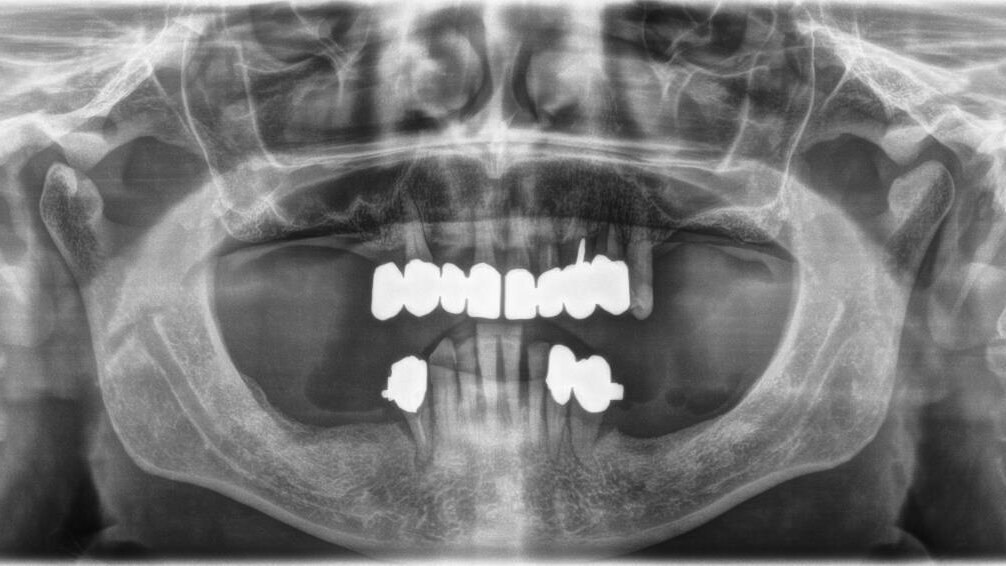

Si effettua solo una ortopantomografia, nessun sondaggio, nessuna valutazione parodontale. Si estraggono i denti, si inseriscono gli impianti, ma… non ci stanno! Tra mille problemi tecnici, diversi operatori e molteplici rifacimenti l’implanto-protesi viene finalizzata dopo oltre 3 anni, ma determina problemi masticatori. Alcune corone si rompono, non è funzionale (il paziente non si riesce a mangiare), fa male, ma soprattutto non piace all’anziano signore.

Inoltre, la protesi traumatizza con le parti metalliche i tessuti molli e la lingua, le corone sono inclinate in senso vestibolare e non occludono alla perfezione. L’overjet è ampio ed è presente un morso aperto anteriore, con trauma sui posteriori. Si vedono i colletti metallici degli impianti, metallo compare negli spazi interprossimali (corone ed impianti non sono in linea)(Figg. 2-4).